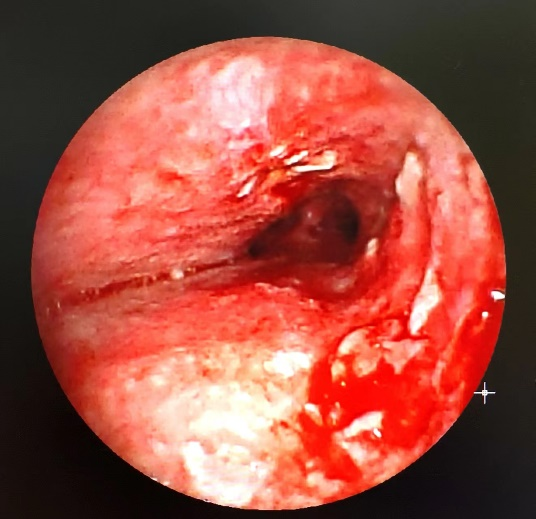

術后1周

1周以后,患者進行了第二次氣管鏡,我們發(fā)現(xiàn)腫塊已經(jīng)大部分消退,予清理肉芽組織,患者術后癥狀明顯改善,咳嗽明顯緩解,也可平臥入睡。